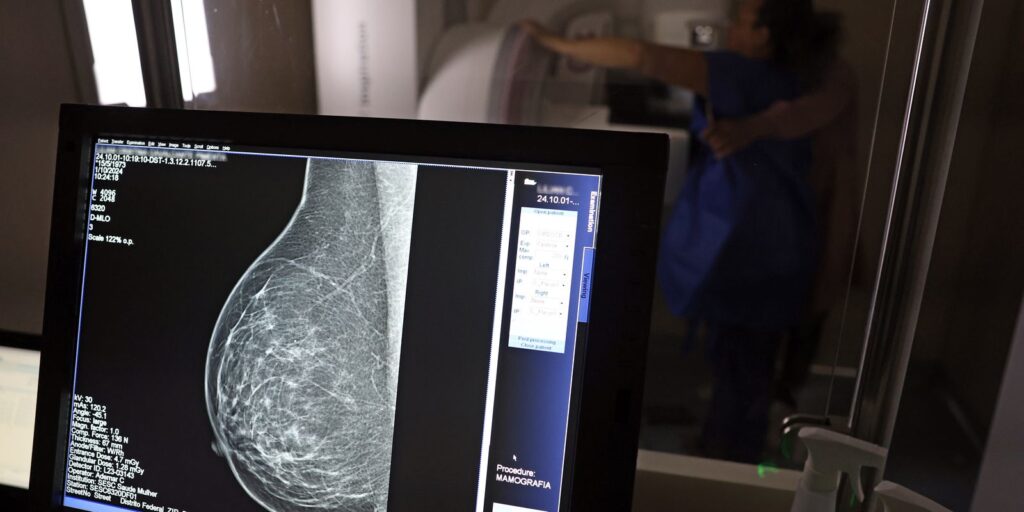

No mês de conscientização sobre o câncer de mama, um relatório destaca a importância de acesso igualitário ao rastreamento e tratamento da doença. Segundo o Atlas da Radiologia no Brasil, do Colégio Brasileiro de Radiologia e Diagnóstico por Imagem (CBR), o acesso aos mamógrafos ainda é um desafio.

O país tem 6.826 equipamentos registrados, sendo 96% em funcionamento. Metade deles está disponível no Sistema Único de Saúde (SUS), responsável por atender 75% da população. Isso equivale a 2,13 mamógrafos por 100 mil habitantes dependentes do SUS.

Na saúde suplementar, que cobre 25% da população, o cenário é mais favorável: 6,54 aparelhos por 100 mil beneficiárias, quase o triplo da rede pública. O Acre exemplifica essa disparidade — são 35,38 mamógrafos por 100 mil habitantes na rede privada, contra 0,84 no SUS.

O Brasil tem uma cobertura muito baixa de mamografias: 24%. O ideal recomendado pela Organização Mundial da Saúde é de 70%. Mesmo em lugares como o estado de São Paulo, que tem a maior concentração de mamógrafos do país, a taxa gira em torno de 26%.

Em setembro, o Ministério da Saúde ampliou as diretrizes de rastreamento, recomendando que mulheres entre 40 e 49 anos realizem mamografias, mesmo sem sintomas. De acordo com o Instituto Nacional do Câncer (Imca), mais de 73 mil mulheres recebem o diagnóstico de câncer de mama anualmente no Brasil.